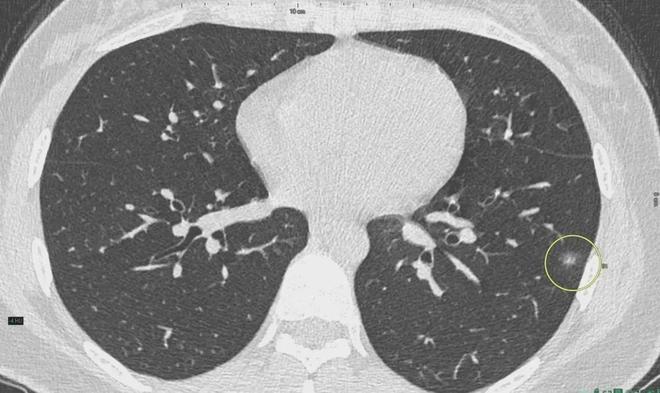

肺結(jié)節(jié)是一種常見(jiàn)的肺部疾病,其發(fā)病率逐年上升,雖然肺結(jié)節(jié)多數(shù)情況下是良性的,但也有可能惡化為肺癌,了解肺結(jié)節(jié)的形成原因?qū)τ陬A(yù)防和治療具有重要意義,本文將為您詳細(xì)解析肺結(jié)節(jié)的形成機(jī)制。

環(huán)境因素是肺結(jié)節(jié)形成的重要原因之一,長(zhǎng)期暴露于污染環(huán)境中,如空氣污染、化學(xué)污染等,可能導(dǎo)致肺部吸入有害物質(zhì),從而引發(fā)肺結(jié)節(jié),長(zhǎng)期接觸石棉、硅塵等職業(yè)環(huán)境因素也可能增加肺結(jié)節(jié)的發(fā)病風(fēng)險(xiǎn)。

遺傳因素也是肺結(jié)節(jié)形成的重要因素,研究表明,家族中有肺癌或肺結(jié)節(jié)病史的人群,其患病風(fēng)險(xiǎn)較高,遺傳缺陷可能導(dǎo)致肺部細(xì)胞異常增生,從而引發(fā)肺結(jié)節(jié)。

生活習(xí)慣對(duì)肺結(jié)節(jié)的形成也有一定影響,長(zhǎng)期吸煙是肺結(jié)節(jié)形成的重要危險(xiǎn)因素之一,煙草中的有害物質(zhì)會(huì)對(duì)肺部造成損傷,導(dǎo)致肺部細(xì)胞異常增生,長(zhǎng)期熬夜、飲食不規(guī)律等不良生活習(xí)慣也可能影響肺部健康,增加肺結(jié)節(jié)的發(fā)病風(fēng)險(xiǎn)。

免疫系統(tǒng)異常也可能導(dǎo)致肺結(jié)節(jié)的形成,免疫系統(tǒng)功能異常時(shí),肺部可能無(wú)法有效清除感染、炎癥等刺激因素,導(dǎo)致肺部組織損傷和修復(fù)過(guò)程失衡,進(jìn)而引發(fā)肺結(jié)節(jié)。